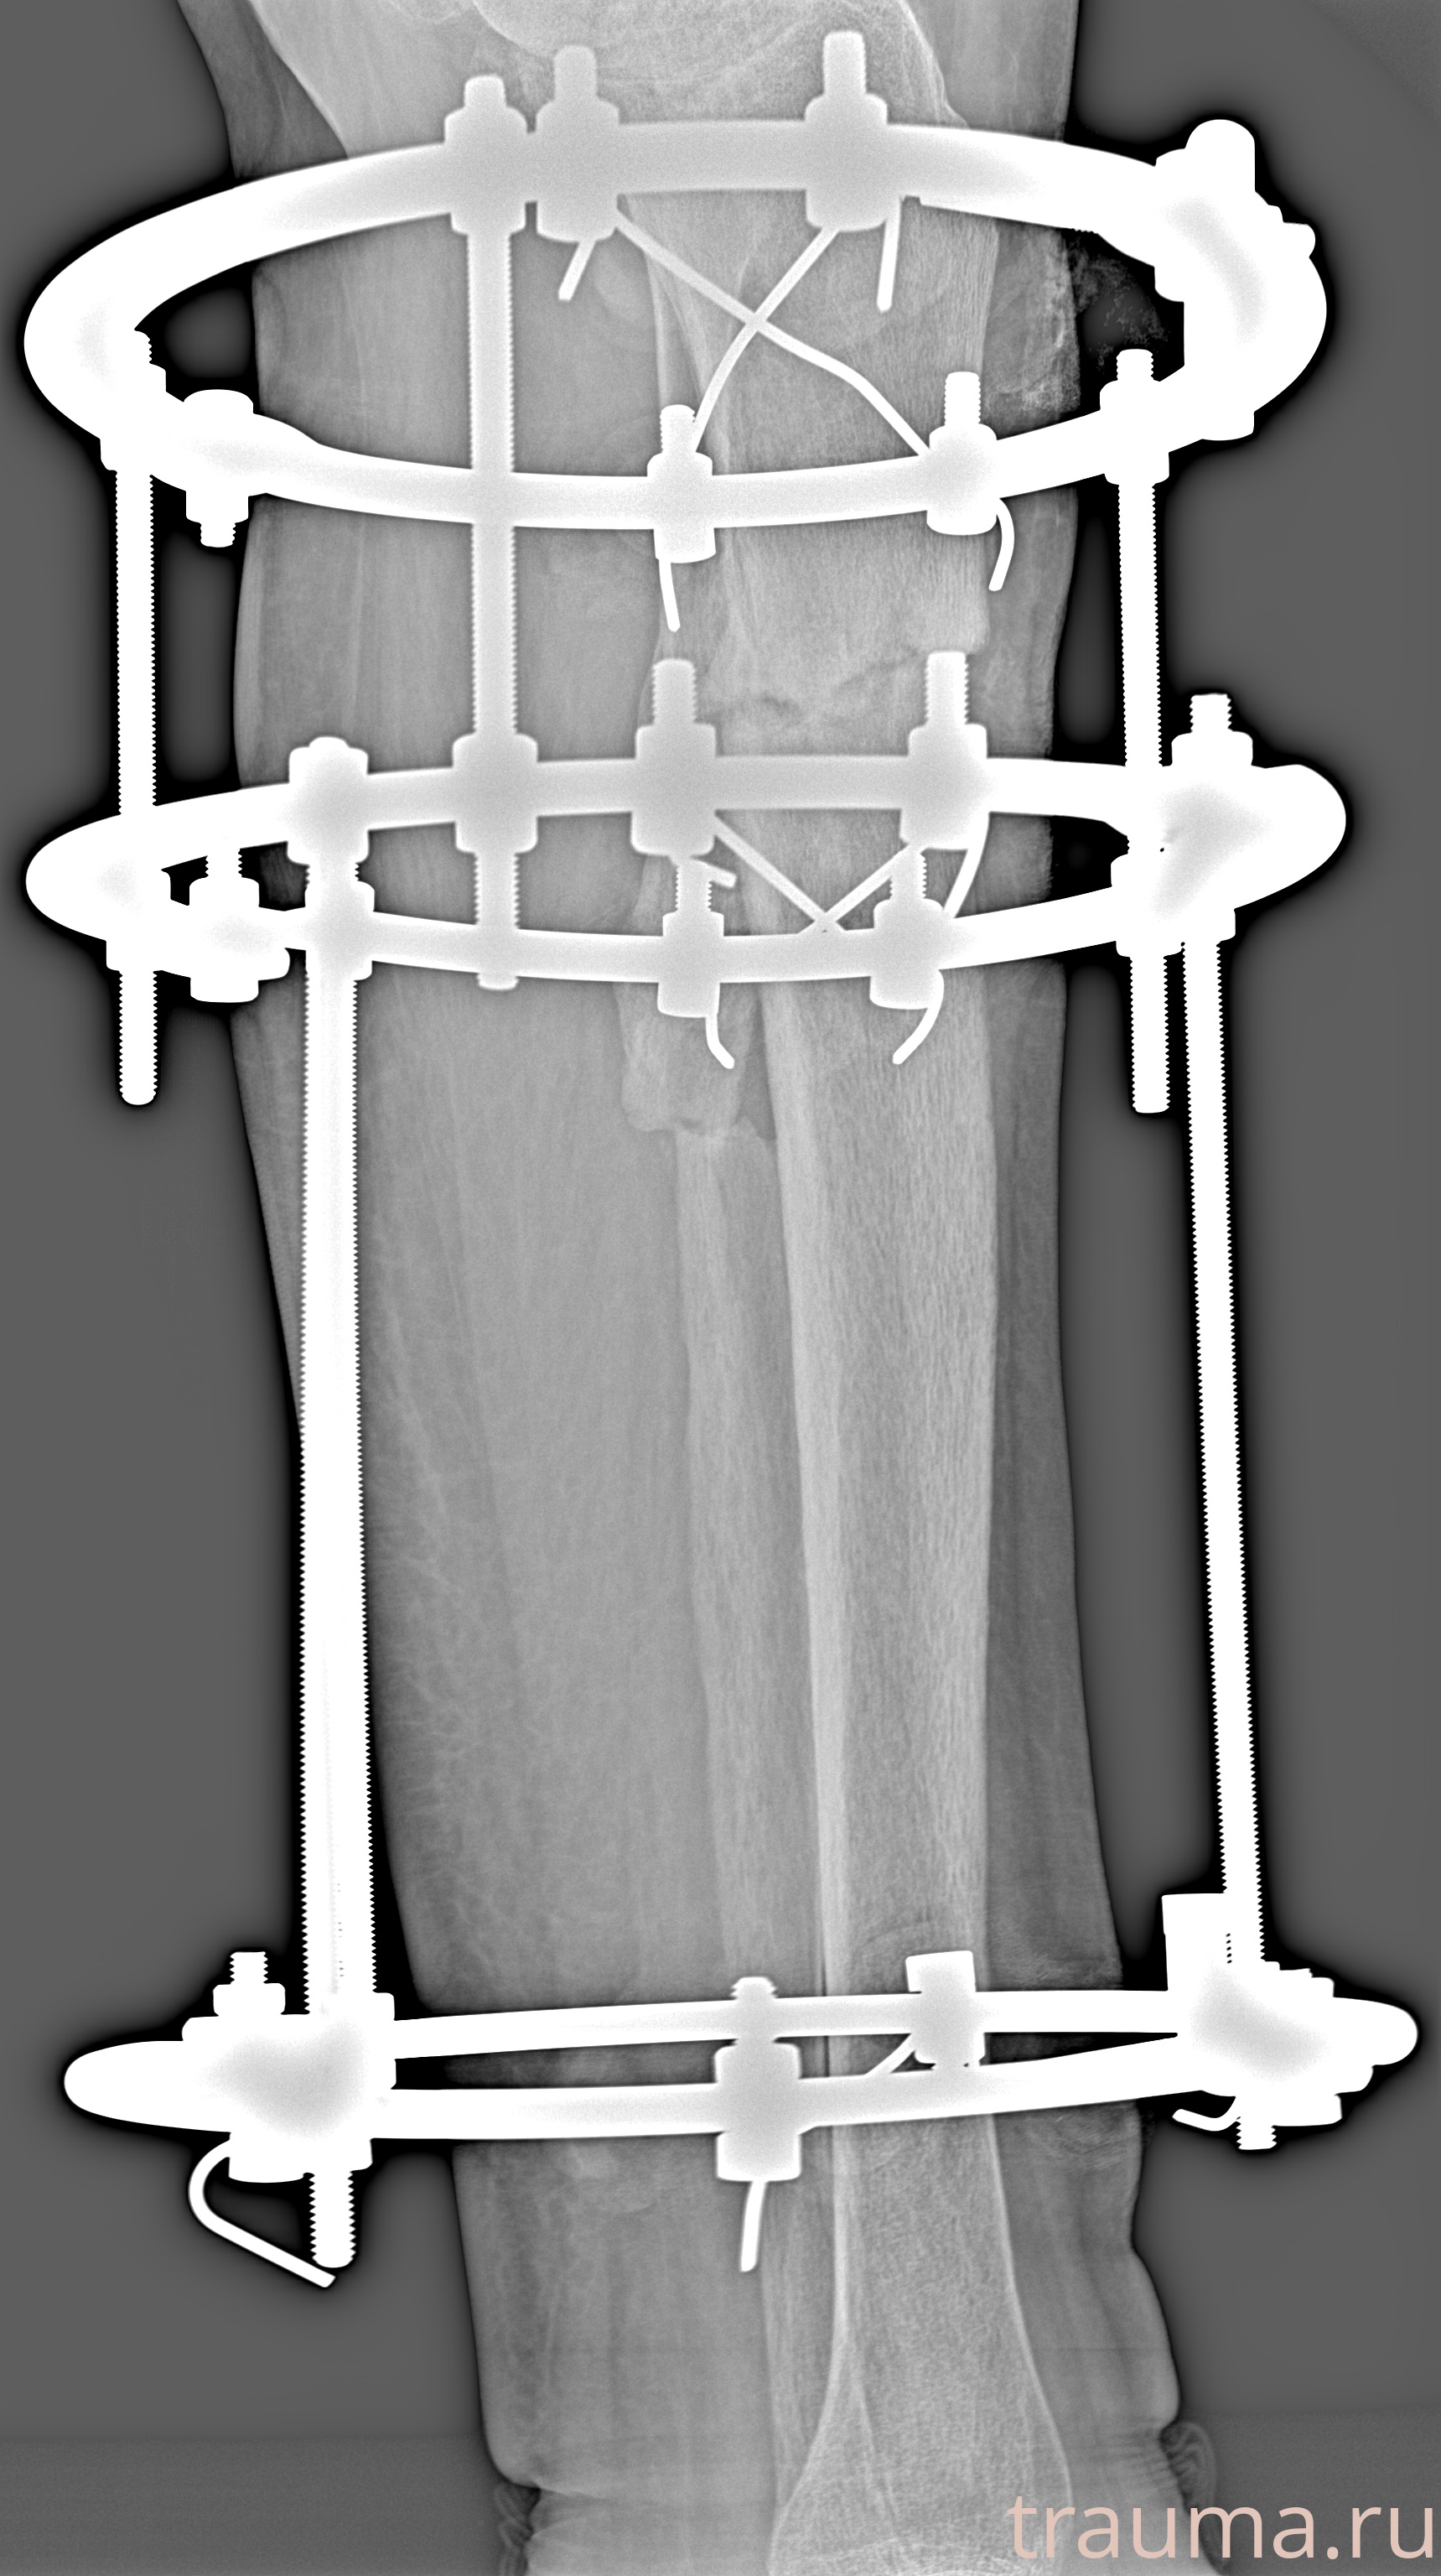

Рентгенограммы

Левая

Рентген на дому: по вашему адресу приезжает врач-рентгенолог, травматолог-ортопед с мобильным рентгеновским аппаратом, проводит диагностику травмы или заболевания, делает необходимые рентгенограммы, дает рекомендации по дальнейшему лечению. Получить качественные снимки в домашних условиях возможно благодаря уникальной методике, разработанной МосРентген Центром для института  Склифосовского